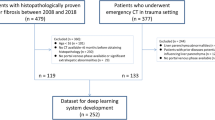

Choi KJ, Jang JK, Lee SS, Sung YS, Shim WH, Kim HS, Yun J, Choi JY, Lee Y, Kang BK, Kim JH, Kim SY, Yu ES (2018) Development and Validation of a Deep Learning System for Staging Liver Fibrosis by Using Contrast Agent-enhanced CT Images in the Liver. Radiology 289 (3):688-697. https://doi.org/10.1148/radiol.2018180763